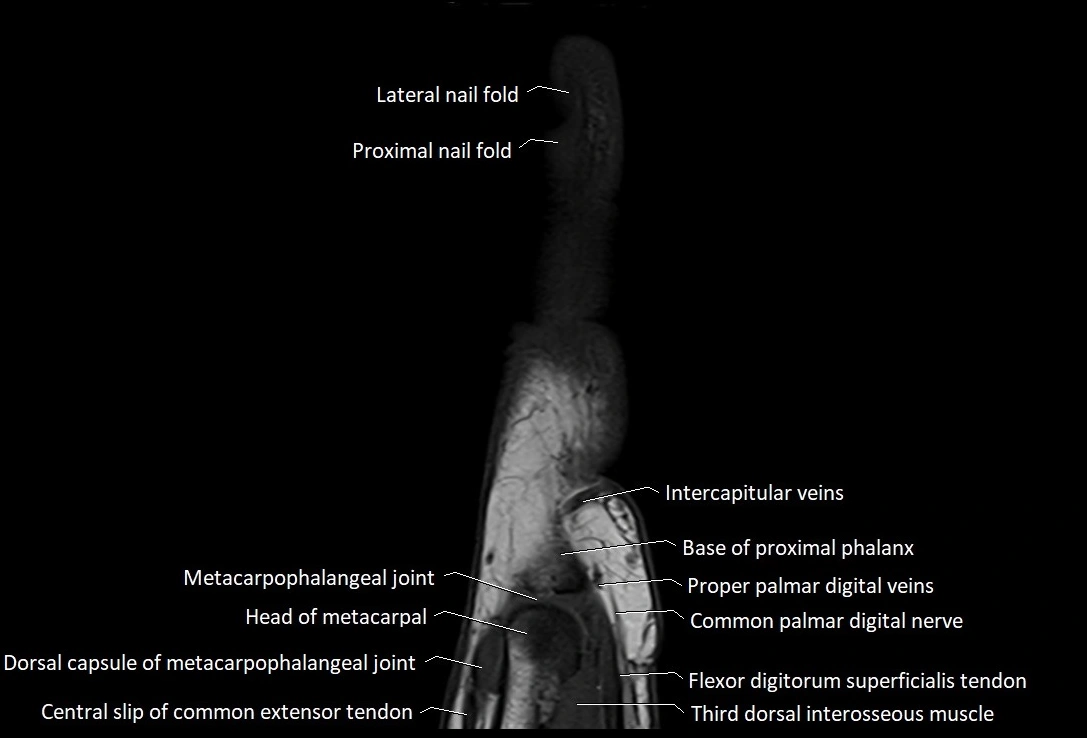

MRI images